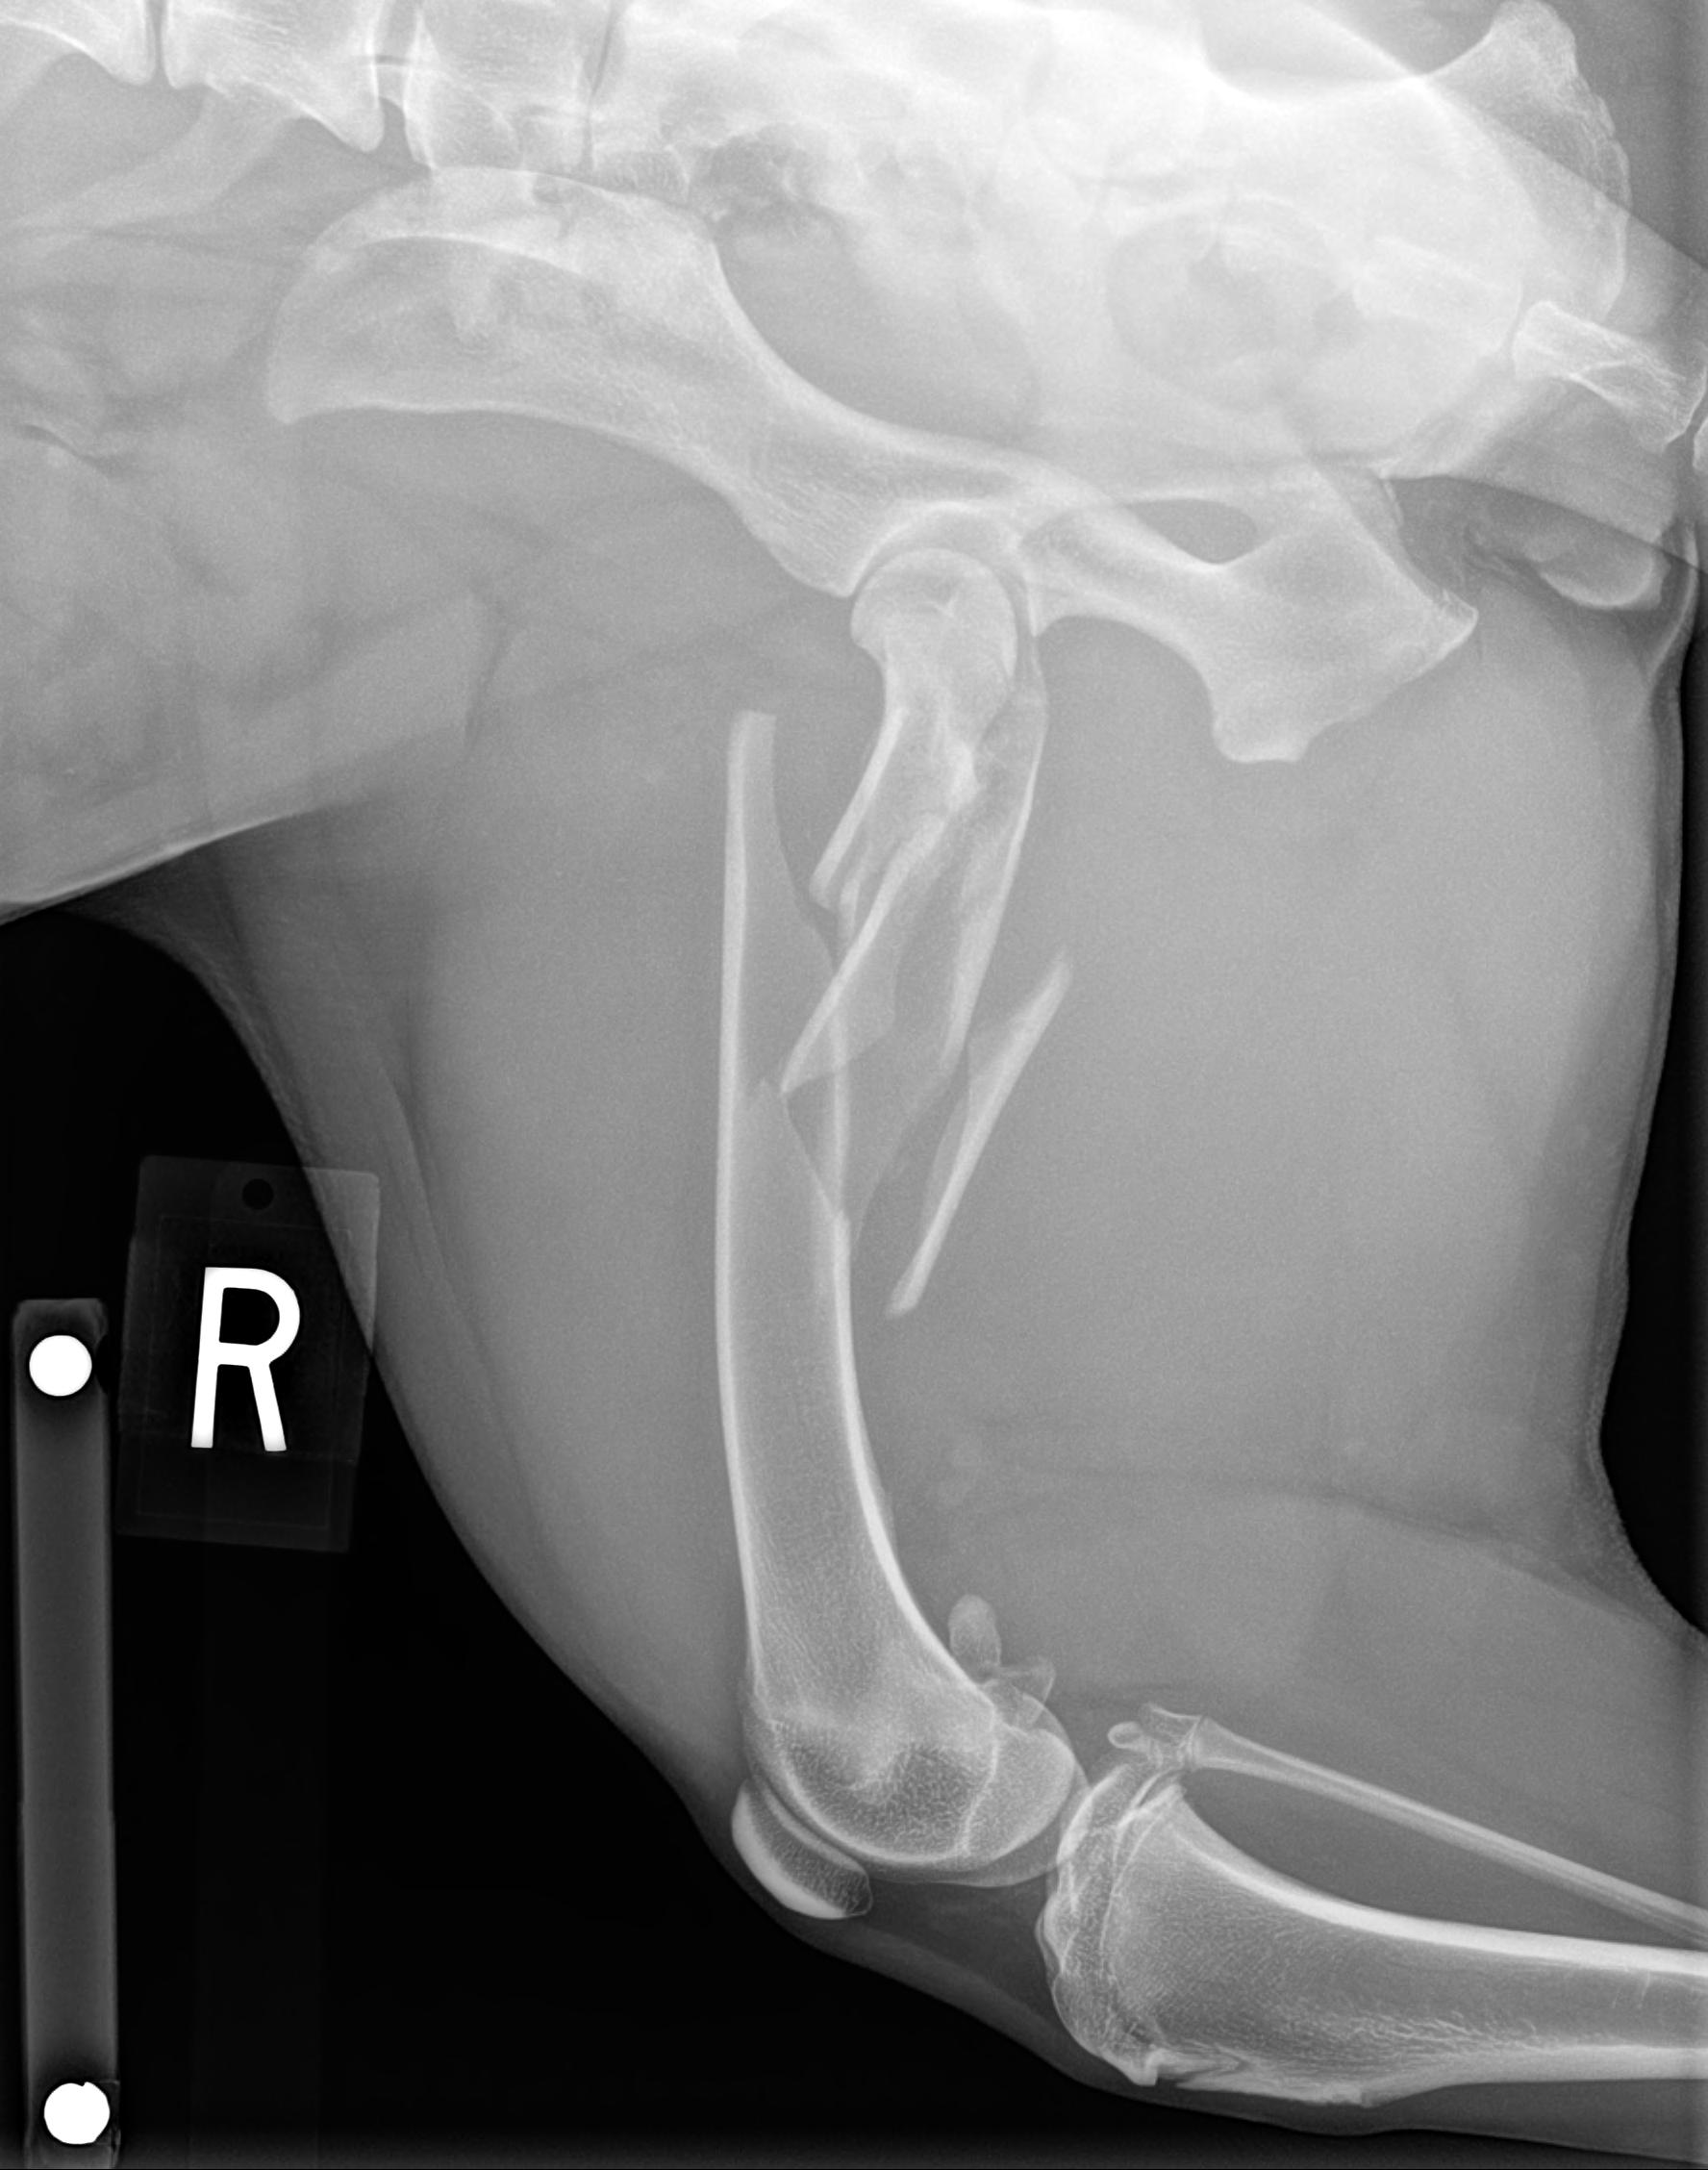

The articles this section pertain to orthopedic (musculoskeletal) topics that tend to be common in veterinary medicine. Please feel free to interact and leave comments. Also, if you would like to see a particular topic, feel free to make a suggestion.